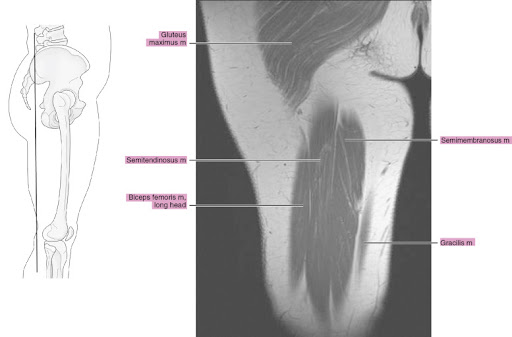

Upper Thigh Muscles Ct Anatomy : Radiological Anatomy X Ray Ct Mri Kenhub, Jun 28, 2021 · there are five muscles in the anterior thigh compartment:. Gracilis, obturator externus, adductor brevis, adductor longus and adductor magnus. Sartorius, and the four quadriceps muscles; These flat muscles are located on the posterolateral aspect of the neck and the posterior upper thorax, overlying the deep muscles of the neck. May 31, 2021 · the superficial muscle layer is composed of the splenius muscles (spinotransversales muscles), which are the splenius capitis and splenius cervicis. One further muscle of the anterior knee is the small articularis genus muscle, it is occasionally is blended with vastus intermedius.

Rectus femoris, vastus medialis, vastus lateralis and vastus intermedius. Sartorius, and the four quadriceps muscles; Gracilis, obturator externus, adductor brevis, adductor longus and adductor magnus. One further muscle of the anterior knee is the small articularis genus muscle, it is occasionally is blended with vastus intermedius. These flat muscles are located on the posterolateral aspect of the neck and the posterior upper thorax, overlying the deep muscles of the neck. The splenius muscles both originate from the. All the medial thigh muscles are innervated by the obturator nerve, which arises from the lumbar Jun 28, 2021 · there are five muscles in the anterior thigh compartment:

Gracilis, obturator externus, adductor brevis, adductor longus and adductor magnus. Sartorius, and the four quadriceps muscles; There are five muscles in this group; The splenius muscles both originate from the. One further muscle of the anterior knee is the small articularis genus muscle, it is occasionally is blended with vastus intermedius. Rectus femoris, vastus medialis, vastus lateralis and vastus intermedius. Mar 14, 2020 · the muscles in the medial compartment of the thigh are collectively known as the hip adductors. Jun 28, 2021 · there are five muscles in the anterior thigh compartment: All the medial thigh muscles are innervated by the obturator nerve, which arises from the lumbar These flat muscles are located on the posterolateral aspect of the neck and the posterior upper thorax, overlying the deep muscles of the neck. May 31, 2021 · the superficial muscle layer is composed of the splenius muscles (spinotransversales muscles), which are the splenius capitis and splenius cervicis. Teachme anatomy part of the teachme series the medical information on this site is provided as an information resource only, and is not to be used or relied on for any diagnostic or treatment purposes.